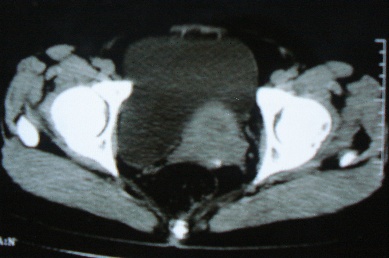

ct10755,女,48岁。感腹胀一周入院。

考虑右侧卵巢囊腺癌并腹腔转移、子宫肌瘤

感觉像是2个病变融合:双侧附件囊腺瘤?

支持:右侧卵巢囊腺癌并腹腔转移、腹水、盆腔积液。

考虑为右侧卵巢囊腺癌并腹腔转移、腹水、盆腔积液.

支持右侧卵巢囊腺癌并腹腔转移(大量腹水)。